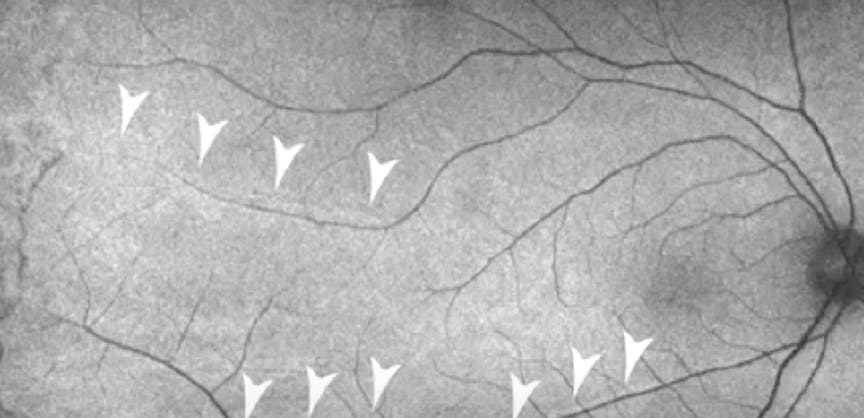

<p>Figure 1. This patient presented with a superotemporal macula-off RRD and was treated with vitrectomy (A). Postoperative FAF demonstrated fine RVPs adjacent to both the superior and inferior arcades (B, arrows). Overlay of ultra-widefield retina images (C) and FAF (D) show that the RVPs correspond to the location of pre-RRD blood vessels.</p>

Figure 1. This patient presented with a superotemporal macula-off RRD and was treated with vitrectomy (A). Postoperative FAF demonstrated fine RVPs adjacent to both the superior and inferior arcades (B, arrows). Overlay of ultra-widefield retina images (C) and FAF (D) show that the RVPs correspond to the location of pre-RRD blood vessels.